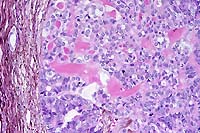

- Case 9-4 . Ganglion. Multifocally neurons have loss

of Nissle substance, with coalescence of the cell cytoplasm as

a central homogenous eosinophilic aggregate surrounded by a clear

to slightly fibrillar halo zone. Nuclei are karyolytic with poorly

defined nuclear outlines. Low to moderate numbers of lymphocytes

and macrophages infiltrate these zones of neuronal degeneration.